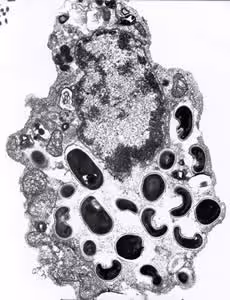

Transmission electron microscopy (TEM) is still the gold standard and is necessary for the identification of the microsporidian species, which is based on internal features of the spore such as the number of polar tubule coils. However, TEM is expensive, time consuming, and not feasible for routine diagnosis.